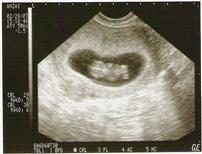

just got back from my first appt and sono

and everything looks great!! I have a new due date of 9/28...6 days earlier! We got to see the heartbeat and the baby was moving around!! I'm so relieved that everything is good so far!! My dr. said i have to watch the weight gain though..I told her i gained 6 pounds so far (it is probably more) and she said to aim to gain 6 pounds the entire first trimester! I feel like a fat cow! Image Attachment(s):